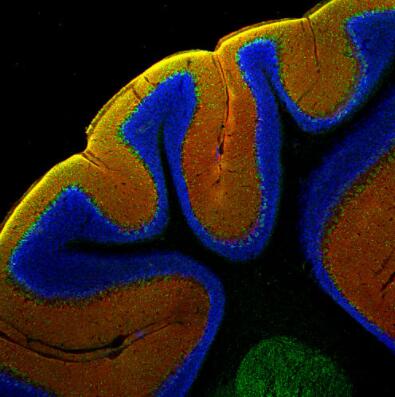

圖8:甲醛固定的小鼠小腦切片(矢狀)兔抗EAAT4抗體(目錄號250 413,稀釋度1:500,紅色)和豚鼠抗Calbindin抗體(目錄編號214 318,稀釋度1:100,綠色)的間接免疫染色。DAPI染色(藍色)顯示細胞核。 | 圖9:甲醛固定的小鼠小腦切片(冠狀)兔抗EAAT4抗體(目錄號250 413,稀釋度1:500,紅色)和豚鼠抗Calbindin抗體(目錄編號214 318,稀釋度1:100,綠色)的間接免疫染色。DAPI染色(藍色)顯示細胞核。 |